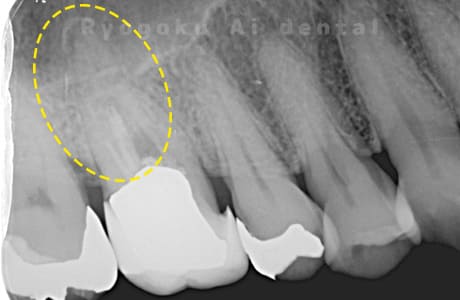

根管内の異物

- 原因

- 根管内異物(ファイル破折)による慢性根尖性歯周炎

- 治療期間

- 3ヶ月

- 治療内容

- マイクロスコープを使用した根管内異物除去並びにマイクロエンド

- 治療費用

- 121,000円(ファイル除去費用も込み)

他院で細い器具(ファイル)が根管内に破折した状態で、咬合痛を主訴に来院された患者様です。ファイルをマイクロスコープ下で除去し、根管治療を行ないました。

<リスク・副作用>

術後は痛み、腫れ、痺れなどの副作用が生じる場合があります。症状が再発する可能性があります。